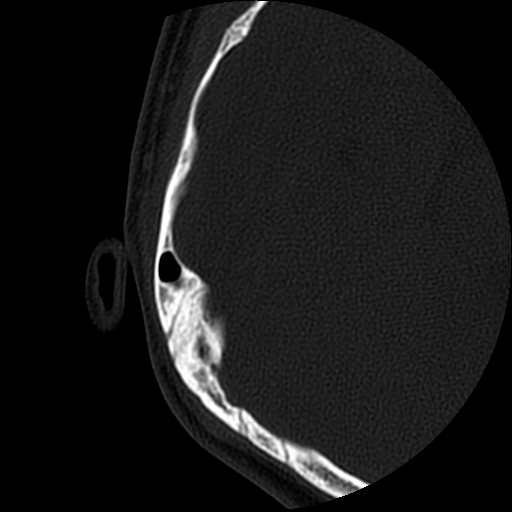

以下是引用随光逐影在2009-8-19 7:25:00的发言:[br]右侧慢性中耳乳突炎,右侧中耳腔及外耳道肉芽肿或胆脂瘤形成。